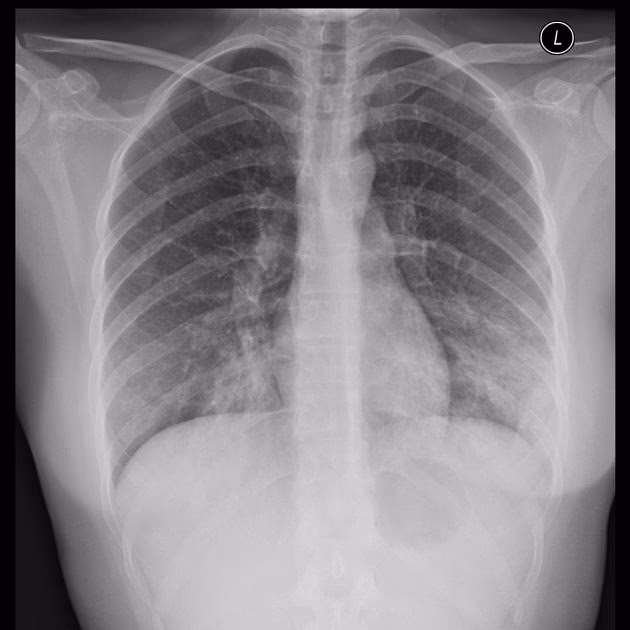

At diagnosticere en Mycoplasma pneumoniae-infektion kan være en udfordring for læger. Symptomerne er ofte uspecifikke og kan ligne mange andre luftvejsinfektioner forårsaget af vira eller andre bakterier. Der er ingen konstante fund ved en fysisk undersøgelse, og røntgenbilleder af lungerne kan vise forskellige mønstre, fra lette interstitielle infiltrater til mere tætte konsolideringer.